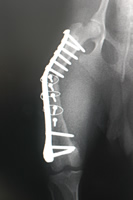

|

| 7)再度のOPです。 3mm厚のバトレスプレートを自作し、前回の破綻した部位の近位そして遠位にはホールを開けず強度を持たせ、骨折部は整理し海綿骨の移植を行いました。万全を期して2カ月の入院予定です。 また、患犬に負担を掛けずに簡単なバンテージで患肢に殆ど負荷を掛けない方法を見つけました。(企業秘密?)  |

![]()  |